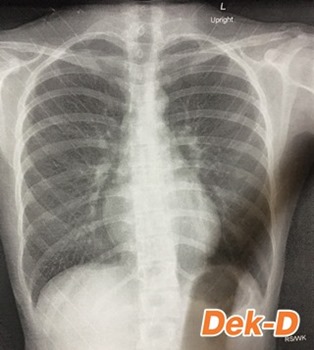

ผู้ป่วยกระดูกสันหลังคดในประเทศไทย มีมากถึง 2-3% ของประชากรเลยทีเดียวค่ะ ความน่ากลัวของโรคนี้คือ เป็นกันโดยไม่รู้ตัว และเริ่มเป็นในช่วงวัยเด็ก ถ้าไม่ได้รับการรักษาโดยแพทย์เฉพาะทาง จะมีผลกระทบต่อสุขภาพ ถ้าปล่อยให้คดมากขึ้นเรื่อยๆ นอกจากจะบุคลิกเสียแล้วยังกระทบกับอวัยวะภายใน เช่น ระบบทางเดินหายใจ ระบบหัวใจ จนถึงขั้นเสียชีวิตได้ เพราะหายใจไม่สะดวกและหัวใจทำงานหนัก

สำหรับอาการที่จะเกิดขึ้นในผู้ป่วยโรคกระดูกสันหลังคด จะมีตั้งแต่อาการปวดหลัง เนื่องจากกล้ามเนื้อในแต่ละส่วนแบกรับน้ำหนักไม่เท่ากัน ซึ่งในรายที่เป็นมากๆ จะปวดหลังเป็นประจำ รวมทั้งมีแนวสะโพกเอียง รูปร่างไม่ได้สัดส่วนคล้ายคนพิการ หอบเหนื่อยง่ายเนื่องจากมีปัญหาทางระบบหายใจ และอาจเป็นโรคปอดอักเสบได้ด้วย